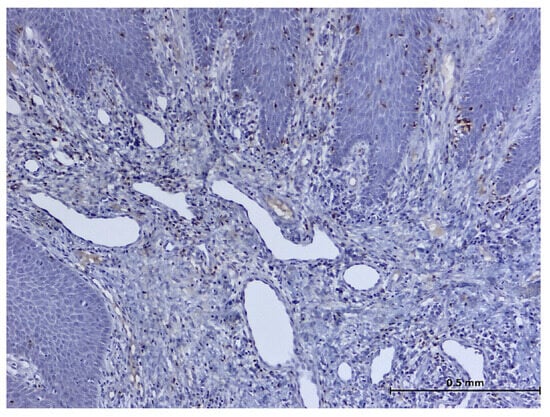

3. Results